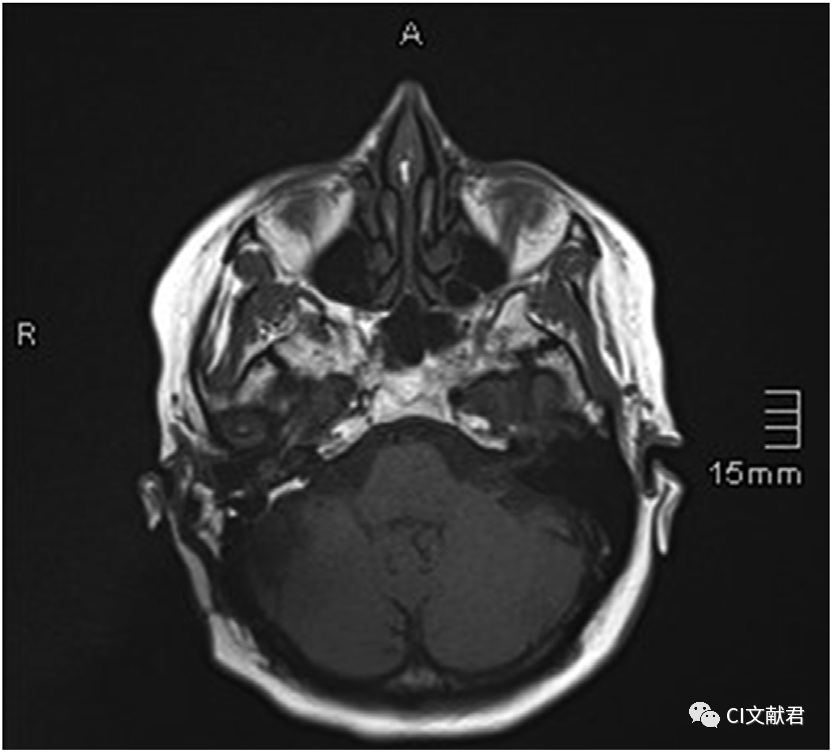

去伪影扫描技术

图片中的患者接受了人工耳蜗植入(奥地利MED-EL Mi1200 Synchrony)和前庭神经鞘瘤切除同期手术。在术后半年因复查肿瘤情况行磁共振检查。在磁场强度1.5T的磁共振机上分别进行了2次扫描,第一张图为采用普通扫描技术获得的影像,第二张图为采用伪影消除扫描技术获得的影像。可以看出人工耳蜗磁铁和金属材料造成的伪影几乎完全消除。而患者没有因此接受任何形式的二次手术。